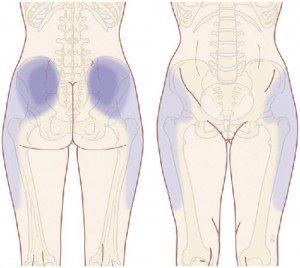

Abdominal Aortic Aneurysm

Potential pain sites associated with abdominal aortic aneurysm. Back pain is present in around 50% of pre-rupture aneurysms. Buttock and thigh symptoms may be referred from the vessel itself. Calf pain may be a result of distal embolization.

An abdominal aortic aneurysm (AAA) is a potentially life-threatening condition. While it typically causes abdominal pain, it can radiate to the lower back. Treatment may include surgery to repair the aneurysm.